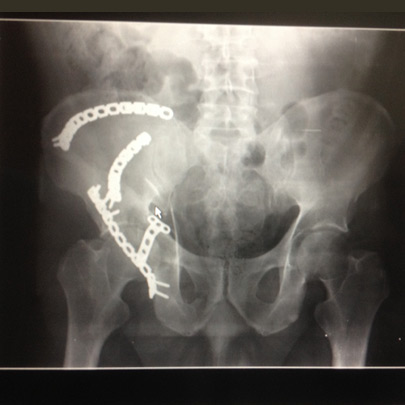

Fracturas y luxaciones

Tratamientos quirúrgicos